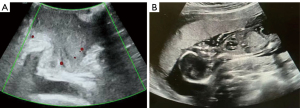

A 32-year-old pregnant woman was admitted to West China Second University Hospital due to a vaginal mass. The patient had a resection of a vaginal mass 10 years previously, which was pathologically diagnosed as a highly cellular leiomyoma. She had no recurrence during the 10 years of follow-up. Fourteen weeks previously, she became pregnant and noticed a gradually developing mass on the same side of the vagina. Physical examination revealed a mass measuring 6 cm × 6 cm × 5 cm in size at the vaginal orifice, originating from the left vaginal wall (Figure 1A,1B). Ultrasound imaging suggested an intrauterine pregnancy and a vaginal mass approximately 5 cm in size (Figure 2A,2B). There was no leiomyoma in the uterus. Surgical intervention was indicated due to a progressively growing vaginal mass of undetermined nature during pregnancy, which was obstructing the vaginal orifice, potentially impeding the birth canal and affecting labor progression. A resection of the vaginal mass was performed under general anesthesia. The mass was located beneath the left vaginal mucosa near the orifice, with a clear boundary suggestive of a leiomyoma. The procedure began with an incision in the vaginal mucosa (Figure 3A). Scissors were then used to carefully separate the mass from the vaginal wall (Figure 3B). An ultrasound knife was employed to cut the vessels supplying the mass. (Figure 3C,3D). The mass was completely resected, and the wound surface showed no obvious bleeding (Figure 3E). Finally, the vaginal mucosa was sutured with absorbable stitches (Figure 3F). The appearance of the vaginal area returned to normal (Figure 4A), and the mass had a smooth surface resembling a leiomyoma (Figure 4B,4C). Pathological results confirmed the diagnosis of leiomyoma with degeneration. After the operation, the patient recovered well and showed no signs of impending abortion. She successfully gave birth to a healthy baby girl vaginally at 38+4 gestational weeks. The patient showed no signs of recurrence during the 24-month follow-up period. A detailed timeline outlining the patient’s clinical course is presented in Figure 5. All procedures performed in this study were in accordance with the ethical standards of the institutional and/or national research committee(s), and with the Declaration of Helsinki and its subsequent amendments. Written informed consent was obtained from the patient for publication of this article and accompanying images. A copy of the written consent is available for review by the editorial office of this journal.